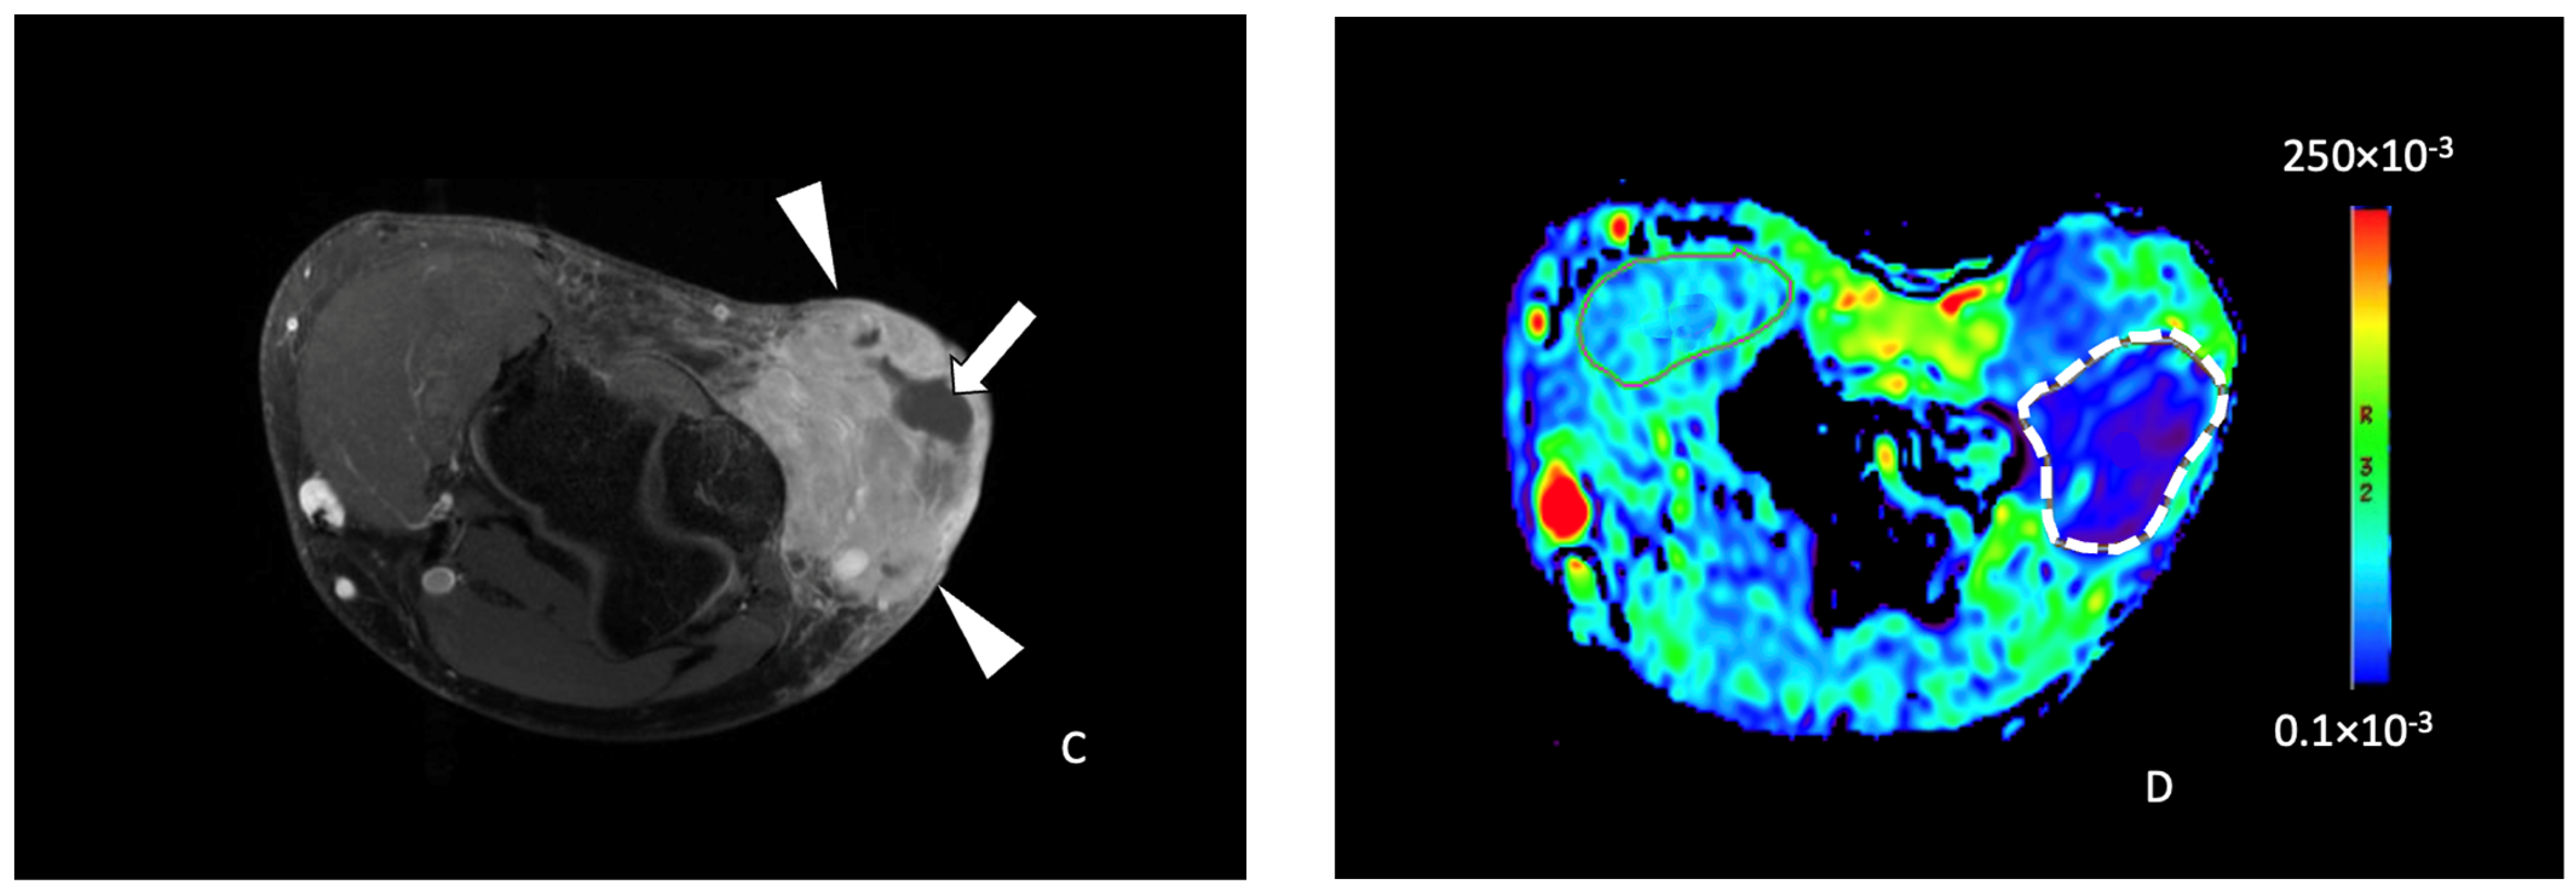

Figure 4.

A 63-year-old female with a liposarcoma issue of the left thigh. Axial T1-weighted (A), T2-weighted fat-saturated (B), and T1-weighted contrast-enhanced (C) MR images showing a large heterogeneous tumor (arrowheads) of the posterior compartment of the thigh, arising from the semitendinosus and semimembranosus muscles containing hemorrhagic components (hyperintense signal T1, arrow in (A), a fat portion on its medial side (star in (A,B)) and small areas of intratumoral necrosis (arrow in (C)). (D) Axial ADC functional map showing a tumor with high ADC value measured at 288 × 10−3 mm2/s in the white dashed lined ROI (>161 × 10−3 mm2/s). The tumor necrosis percentage after neoadjuvant therapy was 60%.